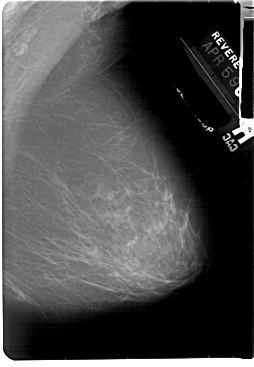

A_1855_1.LEFT_MLO

LEFT_MLO LINES 5491 PIXELS_PER_LINE 3991 BITS_PER_PIXEL 12 RESOLUTION 43.5 OVERLAY

FILE: A_1855_1.LEFT_MLO.OVERLAY

TOTAL_ABNORMALITIES 1

ABNORMALITY 1

LESION_TYPE MASS SHAPE OVAL MARGINS OBSCURED

ASSESSMENT 3

SUBTLETY 3

PATHOLOGY BENIGN

TOTAL_OUTLINES 1

BOUNDARY